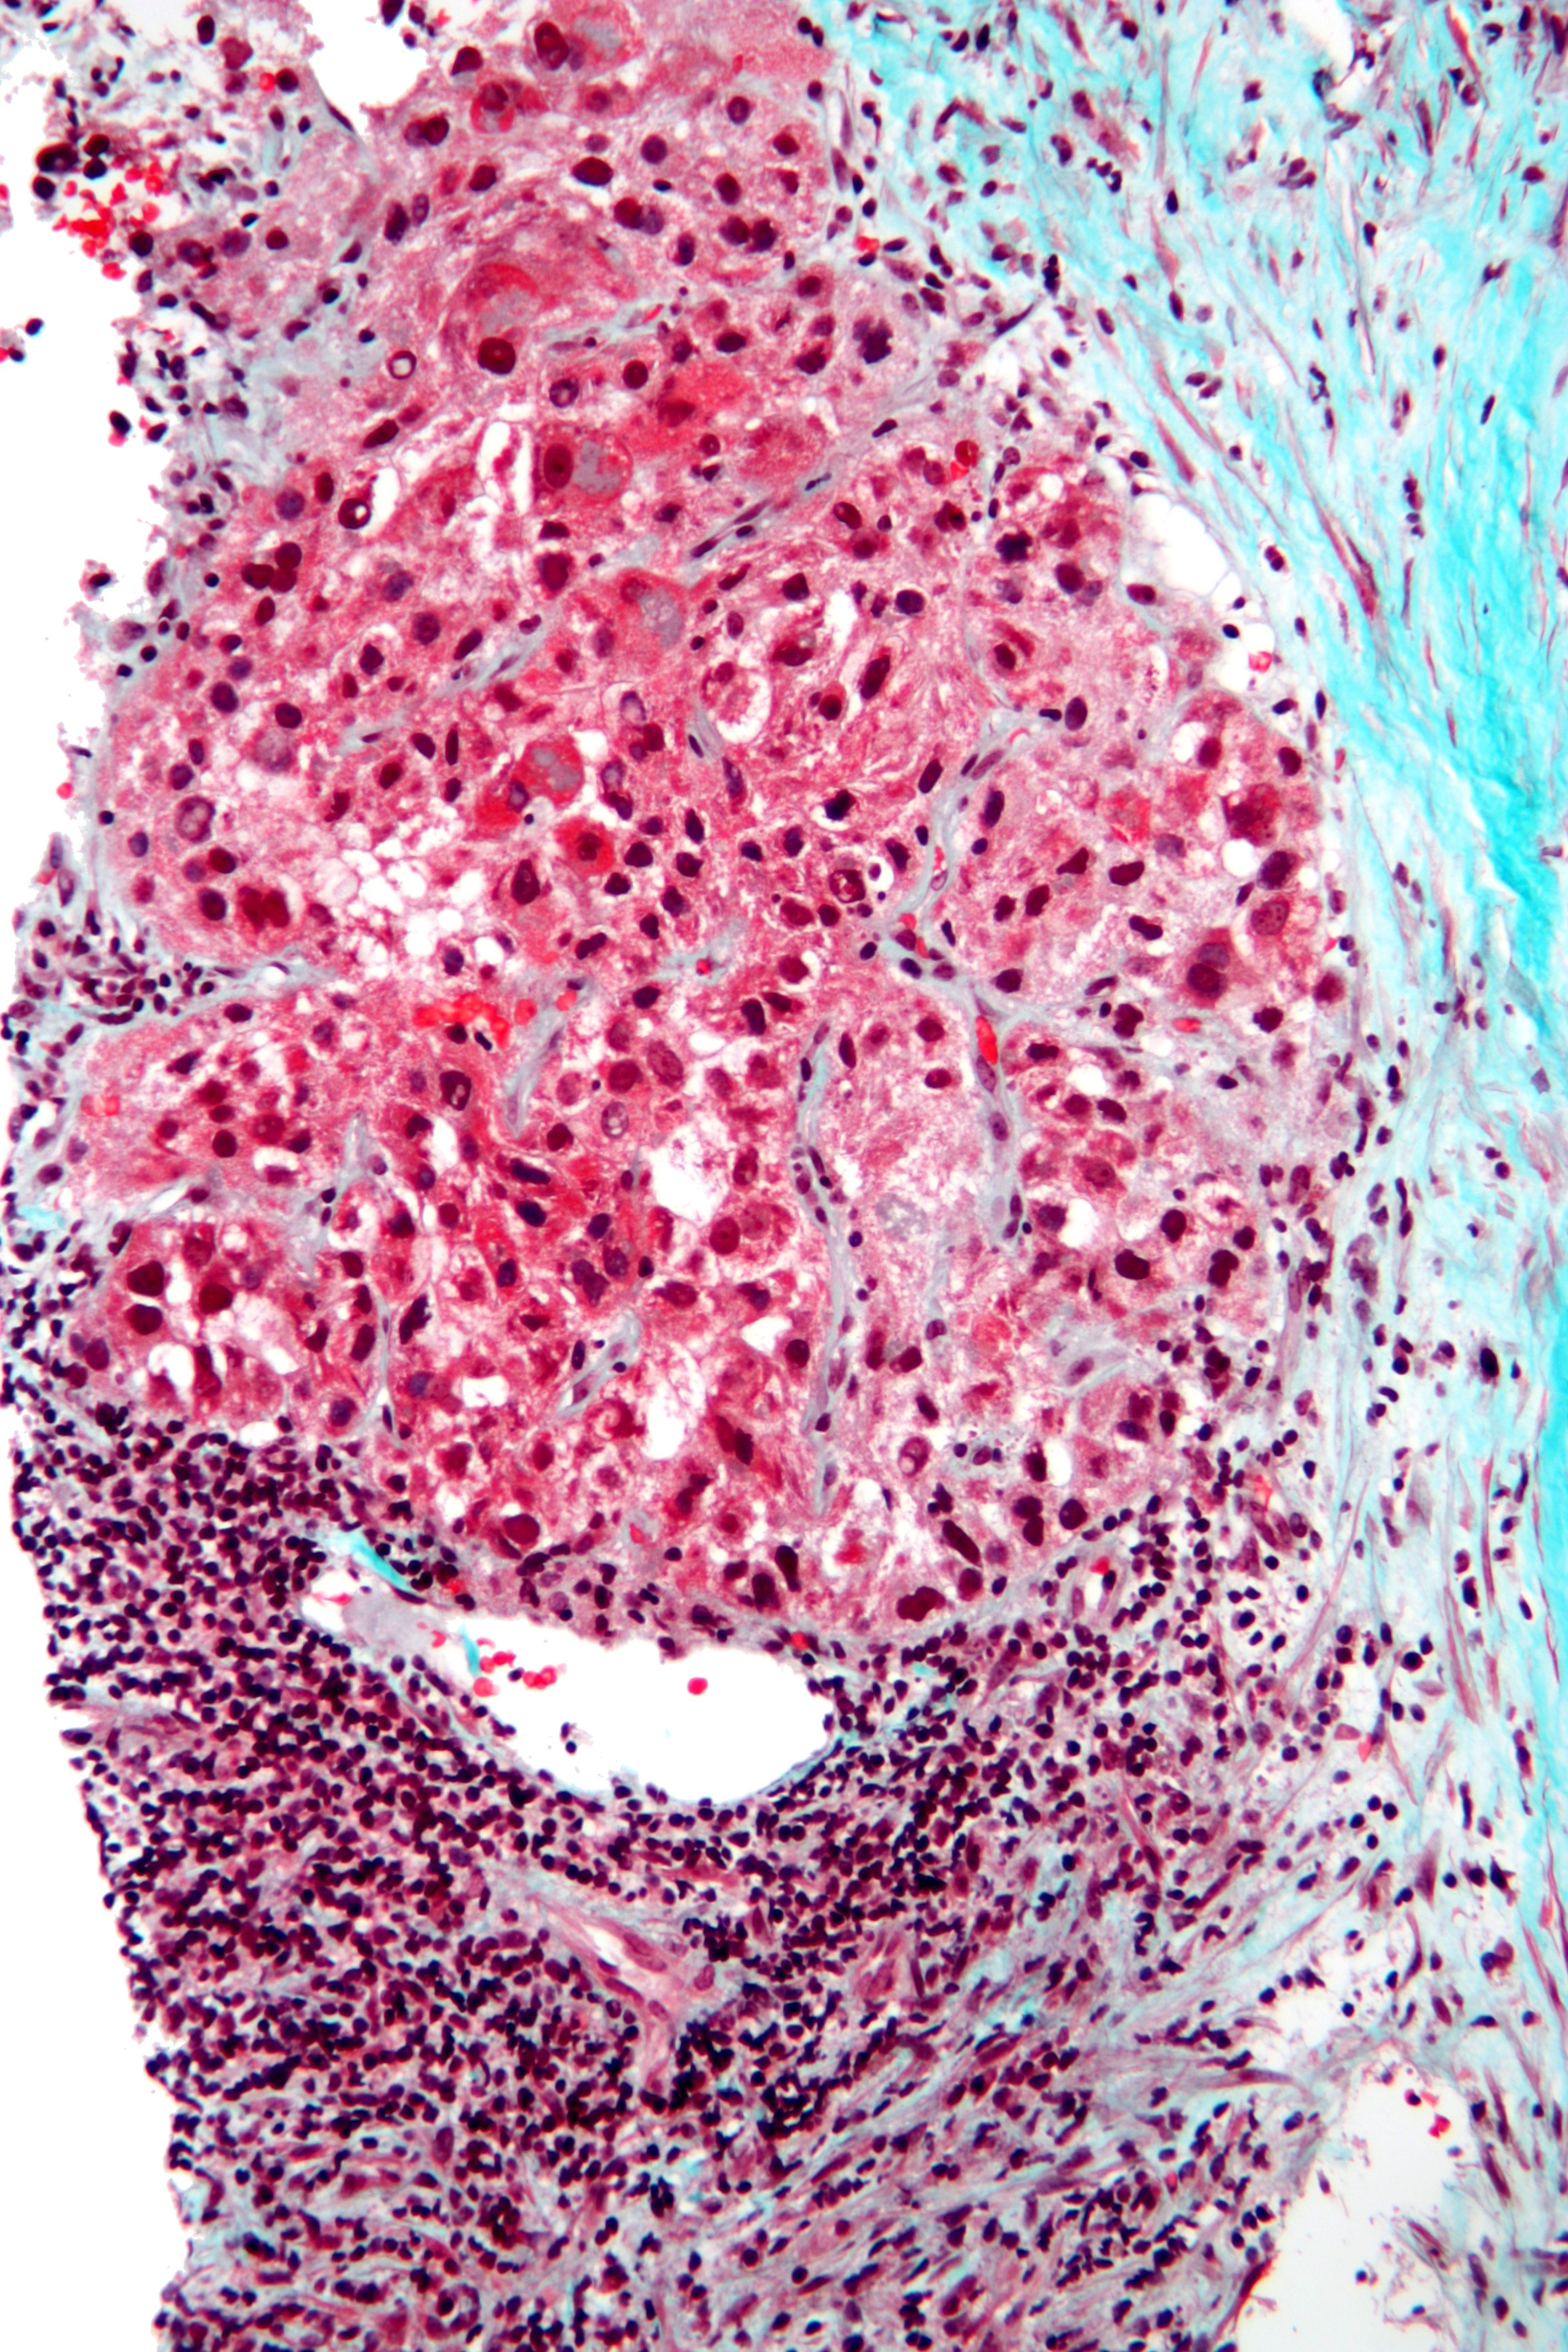

영상 검사에서 간세포암이 의심되지만 확진이 어려운 경우, 조직 검사를 시행하여 확진할 수 있다.[20][42] 그러나 조직 검사는 출혈, 종양 파종 등의 합병증 위험이 있어 모든 환자에게 시행하지는 않는다. 간세포암 진단은 의료 영상의 발전과 함께 발전해 왔으며, 과거에는 종양 생검이 필요했지만, 영상(특히 MRI) 소견은 조직 병리학적 확인 없이도 충분히 결정적일 수 있다.[145]간세포암은 결절성 또는 침윤성 종양으로 나타나며, 결절형은 단일 또는 다발성일 수 있다. 종양 결절은 원형에서 타원형, 회색 또는 녹색이며, 외피는 잘 둘러싸여 있지만 캡슐화되어 있지는 않다. 미만성 유형은 외곽이 잘 둘러싸여 있지 않고 문맥 또는 간정맥에 침투한다 (드물게).[145] 현미경으로 볼 때 간세포암의 네 가지 구조적 및 세포학적 유형은 섬유라멜라형, 선상(아데노이드), 다형성(거대세포), 투명세포이다.[168][169] 잘 분화된 형태의 종양 세포는 간세포와 유사하며 섬유질, 끈, 둥지를 형성하고 세포질에 담즙 색소를 포함할 수 있다. 잘 분화되지 않은 형태의 악성 상피 세포는 원반형, 다형성, 역형성, 거대 세포이다. 종양은 혈관이 잘 형성되지 않아 기질이 부족하고 중심이 괴사한다.[167]